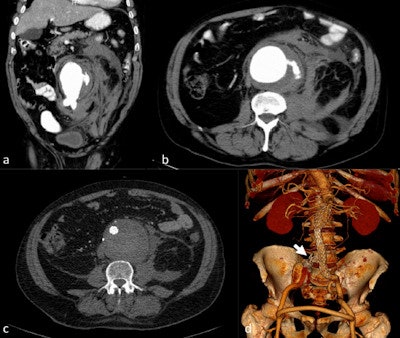

Ruptured aortic aneurysm: The diagnosis of which depends on measurement of the vascular diameter.

Mycotic or infected aneurysms: These rare but life-threatening aneurysms are usually detected when they become symptomatic. They have an atypical morphological presentation, as saccular aneurysms, eccentric aneurysms, or pseudoaneurysms, but they may also present as grotesque fusiform aneurysms.